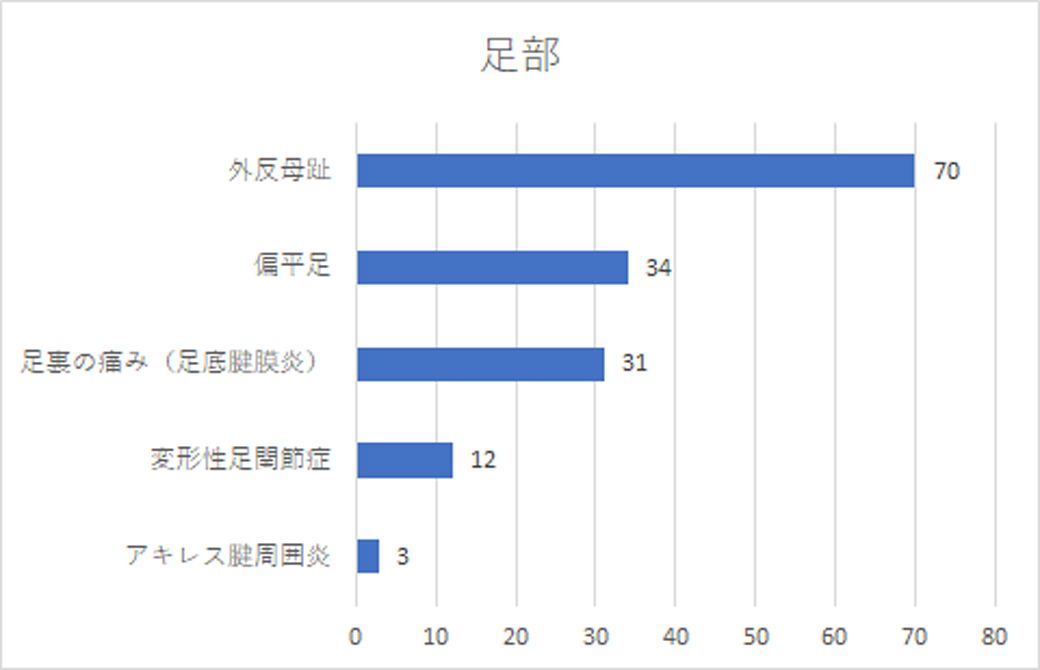

足部|圧倒的な1位は外反母趾

また、足首から下の足部の部門では、外反母趾が圧倒的な1位に。足の母指の先が人差し指のほうに「くの字」に曲がり、つけ根の関節の内側の突き出したところが痛くなる外反母趾。ひどくなると靴を履いていなくても痛むようになります。

外反母趾の一番の原因は靴を履くこと。幅の狭いつま先が細くなった靴を履くと母指のつけ根から先が圧迫されて変形してしまいます。特にヒールの高い靴などは、これをひどくしてしまうため、履く靴には注意が必要です。

昔は靴を履くことが多い、欧米人の疾患だったそう。ひどくなると手術になることもあるので、早めの対処が必要です。

次いで、偏平足。足の裏には土踏まずという、立った際に足の裏で床にふれないくぼんだ部分があります。そのアーチが無くなり、足裏が平べったくなるのが特徴。扁平足の症状は、歩いたりや運動したりすると足関節の内側が腫れて痛くなります。

この偏平足が原因で、3番目に多かった、足裏の痛み(足底筋膜炎)になることもあるそうです。足底腱膜炎とは、足の裏にある、踵(かかと)と足の指の付け根までを伸びている足底腱膜が炎症をおこし、痛みなどの症状が出る病気です。足底筋膜炎とも呼ばれています。

スポーツはもちろん、長時間立ち仕事をしていたり、足裏に負担がかかることで起こります。